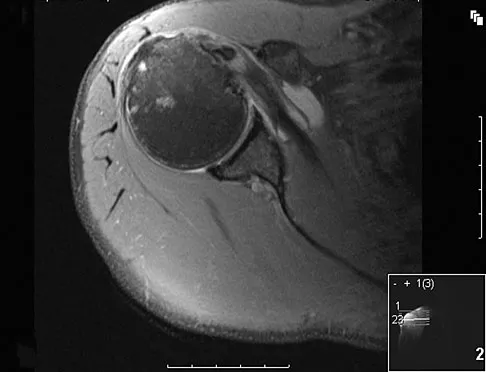

Question 100

A 16-year-old girl has a painful foot mass. A radiograph, MRI scan, and biopsy specimens are shown in Figures 35a through 35d. What is the most likely diagnosis?

Explanation